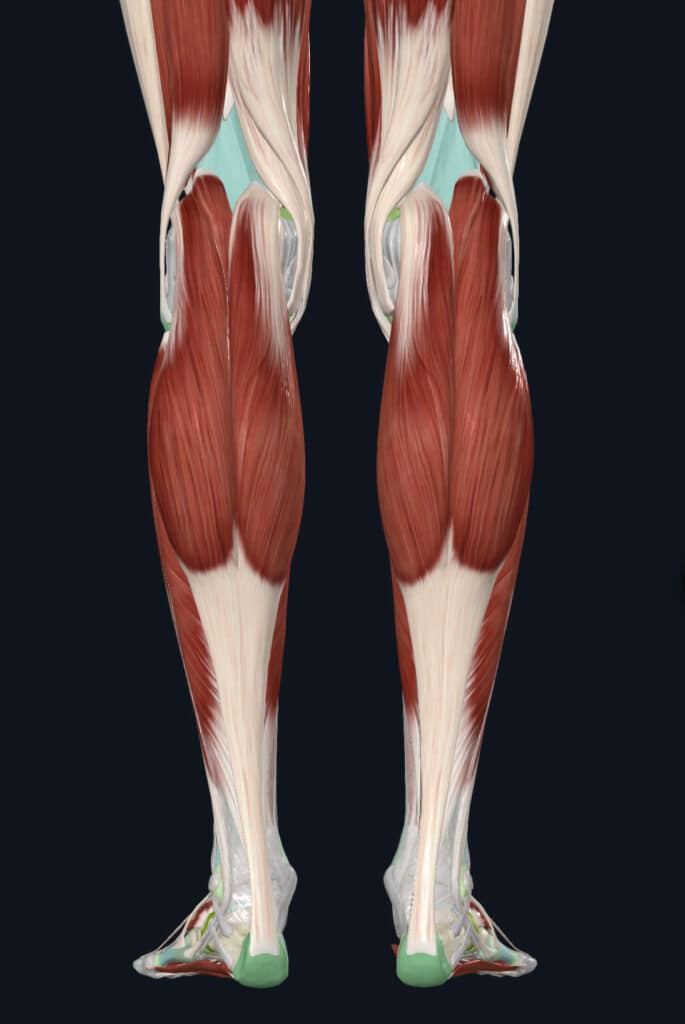

What is the anatomy of the calf?

The calf primarily consists of two large muscle groups - the gastrocnemius and the soleus. Most people think of the gastrocnemius when describing the calf because it is the outermost muscle in the lower leg. It cross the ankle and knee and is involved in bending your knee as well as pointing your foot. The soleus muscle contributes to the push-off when walking or running as it only cross the ankle joint and not the knee. The two muscle groups combine into the Achilles tendon that attaches to the back of the heel. While there are deeper muscle compartments in the lower leg, this article will focus on the gastrocsoleus complex.